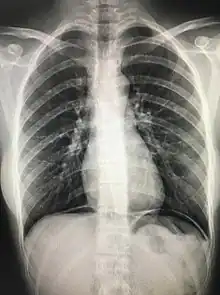

The cupola sign is seen on a supine chest or abdominal radiograph in the presence of pneumoperitoneum.

It refers to dependent air that rises within the abdominal cavity of the supine patient to accumulate underneath the central tendon of the diaphragm in the midline. It is seen as lucency overlying the lower thoracic vertebral bodies. The superior border is well defined, but the inferior margin is not.